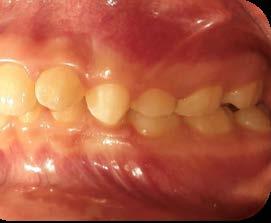

Entre los elementos que conforman al sistema estomatognático, están los dientes caninos, órganos dentales esenciales en la fisiología masticatoria; punto de unión y continuidad estética entre la línea de la sonrisa y el corredor posterior del arco dental, además de que ejercen la función de pilares estabilizadores en la oclusión fisiológica (Figura 1).

Los caninos son indispensables durante los movimientos de lateralidad y vitales para la continuidad de los arcos dentales, tanto en la dentición decidua como en la permanente; son responsables del funcionamiento y la armonía oclusal. Su posición adecuada en el arco asegura un buen contorno de la cara, sonrisa agradable y armónica con la estética facial. (Figura 2).

El canino divide su cara vestibular en 2 vertientes, una mesial que se continúa con los incisivos y otra distal que se alinea con los dientes posteriores, razón por la cual su ausencia genera alteraciones muy importantes en la oclusión y la estabilidad fisiológica del sistema estomatognático (Figura 3).

El trayecto que el canino tiene que recorrer desde su germinación hasta su acomodo final en el arco dental, es largo y complicado, al sortear barreras, alteraciones y modificaciones no previstas, surgidas de factores fuera del proceso natural, (entiéndase esto, como una alteración al código preprogramado del proceso de crecimiento y desarrollo craneodentofacial, por factores externos al organismo), antes de lograr erupcionar y en ocasiones sin obtener oclusión con su antagonista (Figura 5).

El canino a la mitad de su trayectoria de erupción, usa como guía la cara distal de la raíz del incisivo lateral, situación que clínicamente se refleja en la distoinclinación de dicho diente. Sin embargo, si la dimensión de la raíz del diente lateral o su anatomía no es acorde del todo adecuada, la

dirección de erupción se queda a la deriva y por lo regular se dirige hacia el área palatina43 (Figura 6).

Es por lo anterior, que durante el intercambio dentario, la vigilancia periódica, a través de radiografías, análisis de modelos de estudio y una evaluación clínica, son acciones necesarias para la planeación adecuada de un tratamiento interceptivo, en caso de llegar a ser necesario, para generar los cambios y movimientos a nivel ortopédico y ortodóntico respectivamente y así evitar en lo posible una inclusión canina (Figura 7).

En la práctica clínica, al hacer la revisión, uno de los signos clínicos motivo de alerta, correspondería a la falta de movilidad de los caninos deciduos cuando ya es tiempo en el intercambio dental,(caninos superiores 10 años ±9 meses, caninos inferiores 9 años ±9 meses)9 así como señalar si existe la ausencia de los mismos, la falta de espacio en el arco dental para la erupción de los caninos

permanentes, por el que el apoyo radiográfico inicial confirmará la posibilidad de una inclusión canina en proceso (Figura 16).